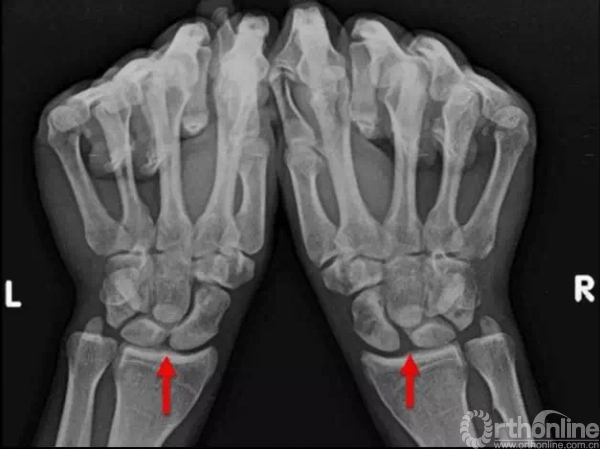

舟月关节脱位在临床中常常容易漏诊,舟月关节脱位诊断时一定要进行双侧的X线对比。